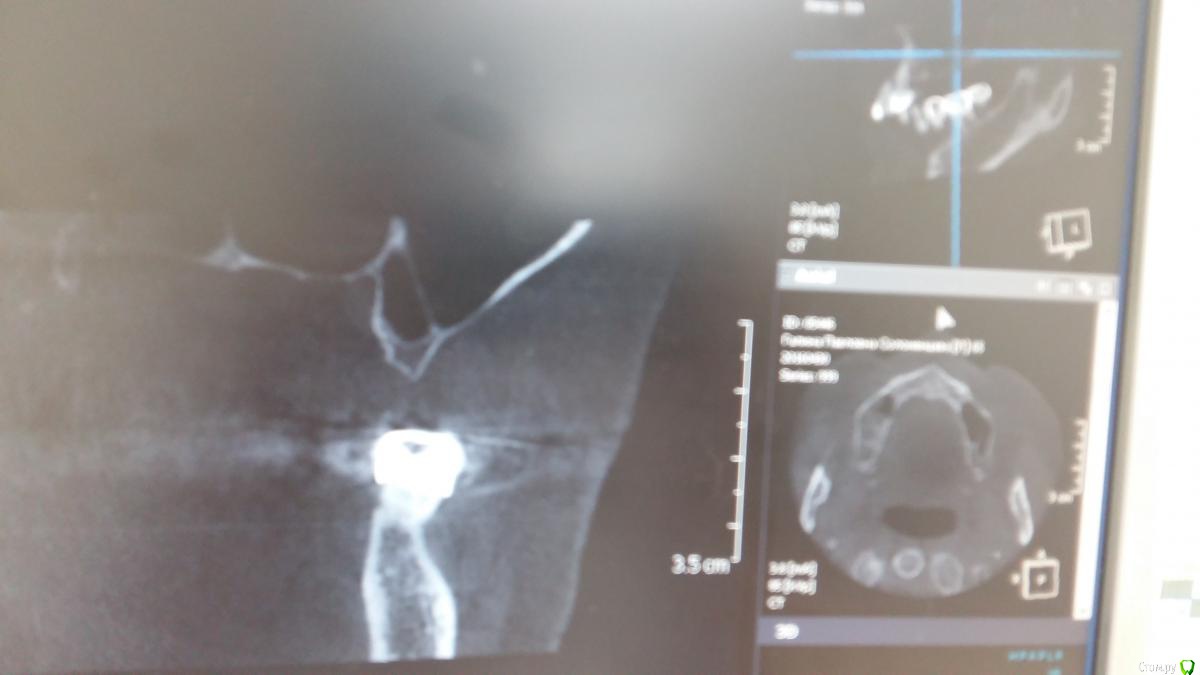

Zubnik7 Опубликовано 30 сентября, 2016 Поделиться Опубликовано 30 сентября, 2016 Подскажите варианты проведения синус лифтинга,корень удален 1 Ссылка на комментарий

Доктор Добрых Дел Опубликовано 30 сентября, 2016 Поделиться Опубликовано 30 сентября, 2016 Одно большое окно, отслойка в обеих камерах, удаление перегородки (части перегородки), отслойка дальше сколько нужно, графт мембраны и т.д. А вообще срезы бы по подробнее - не до конца понятна локализация септы 1 Ссылка на комментарий

Nazim_NV86 Опубликовано 30 сентября, 2016 Поделиться Опубликовано 30 сентября, 2016 Это неполная перегородка. Сделайте овальное окно горизонтально. При отслоении будьте осторожны. С самой перегородки десна будет отслаиваться неохотно. Не порвите. Дальше всё как обычно. Если надорвали, то 2 слоя мембраны на перфу. Ссылка на комментарий

Zubnik7 Опубликовано 30 сентября, 2016 Автор Поделиться Опубликовано 30 сентября, 2016 Перегородка не полная,сейчас выложу новые срезы,более информативные Ссылка на комментарий

Zubnik7 Опубликовано 30 сентября, 2016 Автор Поделиться Опубликовано 30 сентября, 2016 Новые срезы Ссылка на комментарий